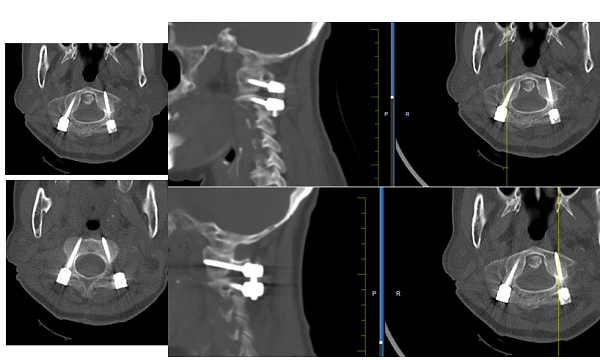

然而,术前检查又现难题:老人寰枢椎及椎动脉走行存在变异,大幅增加了手术难度与风险。为确保手术精准安全,骨外一科团队集体研讨后,决定采用术中三维C型臂联合骨科手术导航系统开展操作。该系统可通过环形扫描获取CT级三维影像,传输至导航系统后为手术提供精准指引;同时搭配高速磨钻匹配导航技术,有效减少椎体位置移动,解决了传统导航工具穿刺精准度不足的痛点。

手术由柏涛主任医师、王国著副主任医师、董谐主治医师联手完成。术中,三维C型臂与导航系统无缝配合,医生在精准指引下完成穿刺置钉,对齿状突骨折进行复位固定,同时采用微创椎体成形术治疗第一腰椎骨折。整场手术高效安全,最大限度地降低了手术创伤。